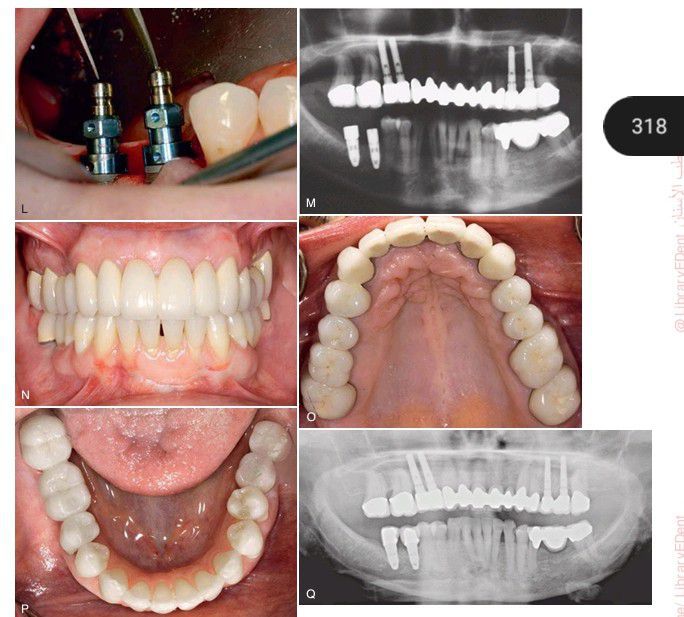

, cont’d (L) Mandibular implant placement. (M) Radiograph after placement of mandibular implants. (N) Frontal view of the completed prosthetics. (O) Occlusal view of the completed maxillary prosthetics. (P) Occlusal view of the completed mandibular prosthetics. (Q) Final radiograph.